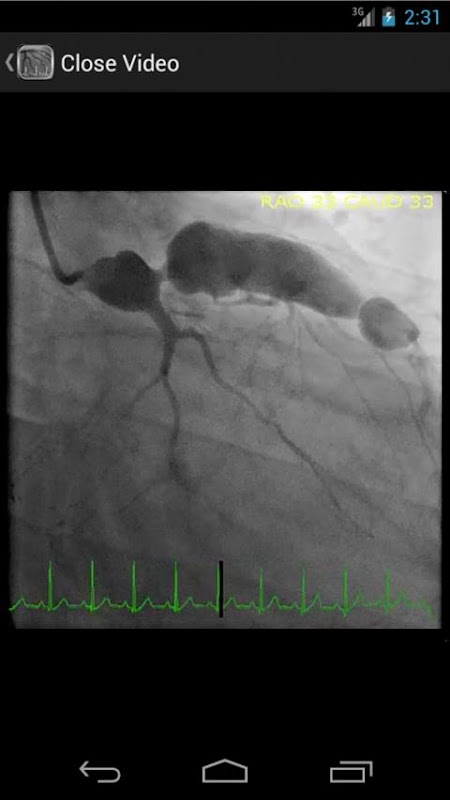

* Pangkalan data dicari yang mengandungi lebih daripada 30 video (angiogram koronari, ventriculograms, dan aortograms) kedua-dua hasil penemuan dan jarang berlaku di makmal catheterization jantung